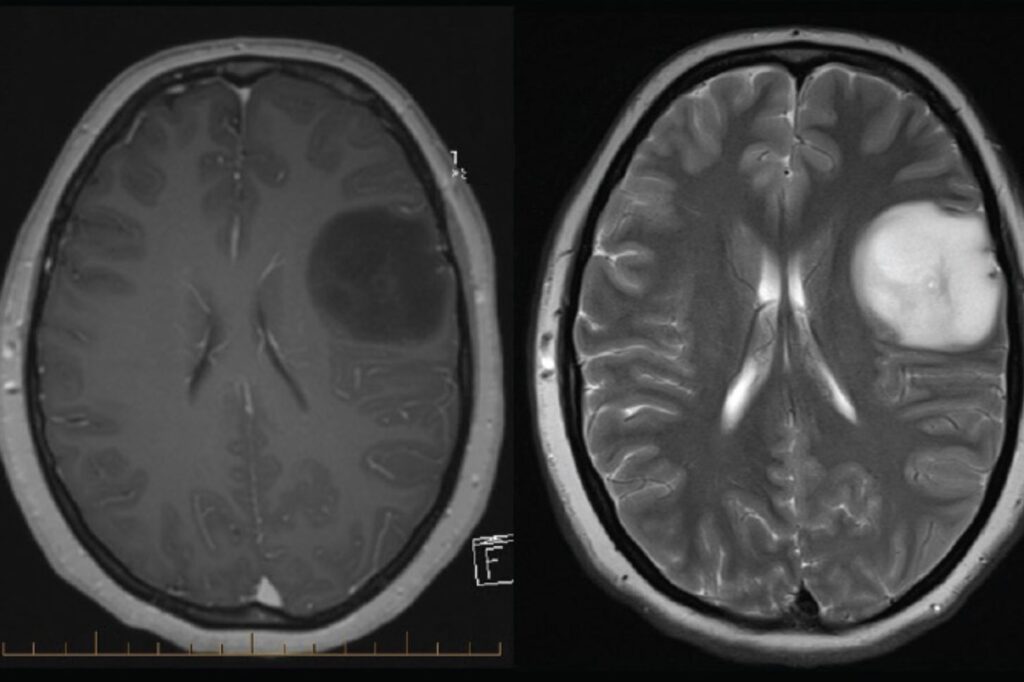

- Rezonans magnetyczny (MRI) – MRI jest uważany za najlepszą metodę obrazowania mózgu przy diagnozowaniu glejaków mózgu. Polega na wykorzystaniu pola magnetycznego do uzyskania bardzo szczegółowych obrazów mózgu, które mogą pomóc w identyfikacji ewentualnych guzów lub nieprawidłowości w tkance mózgowej.

- Tomografia komputerowa (CT) – CT, podobnie jak MRI, może dostarczyć obrazów mózgu, lecz jest on mniej szczegółowy, i często wykorzystywany jest jako uzupełnienie MRI.